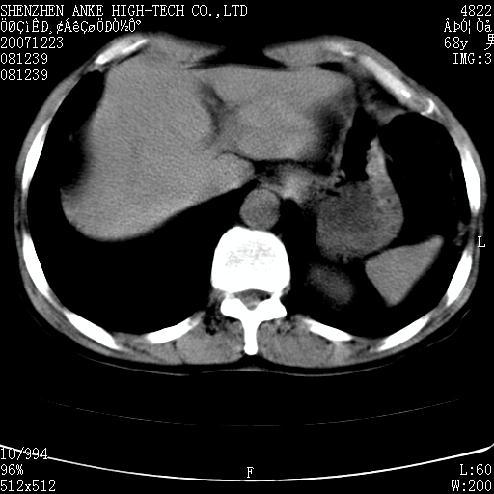

患者:男,63岁,2年前胆囊切除术后,现右上腹部剧烈疼痛近2天.

有无外伤史?右肾包膜下血肿可疑。

主要是问右肾有没有问题?患者无明显外伤史.

未见异常,病人差闭气,伪影较多.

上腹部ct平扫未见明显异常。

肠道准备不好,胃底后壁显示不清,右肾改变考虑为伪影。

请看第一张正位片,胸主动脉象有扩张,胸主动脉瘤?